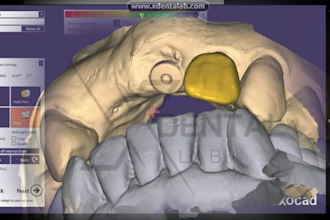

I will do dental prosthesis crown design using exocad, 3shape, inlab and cerec

From $20

Offers video consultations